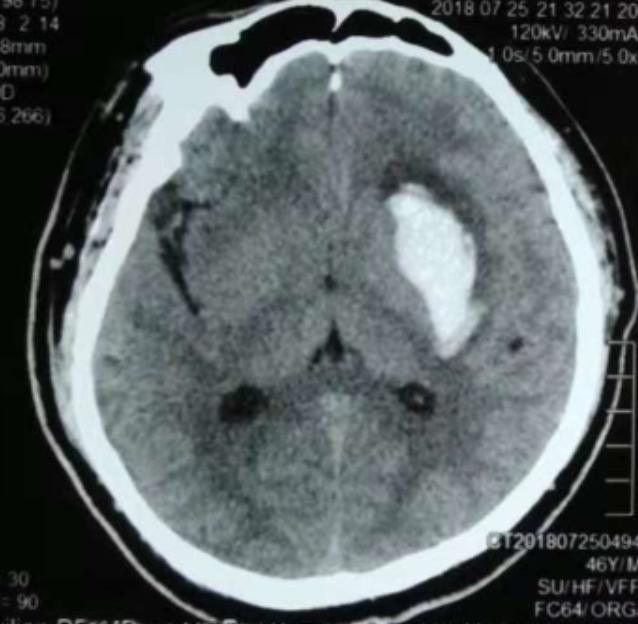

alt text

3個(gè)月前CT:腦出血